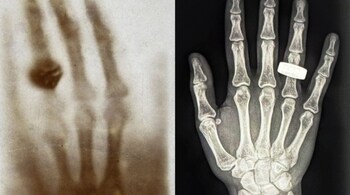

A team of four astronauts took the first X-ray of a human hand in space as they floated high above our planet, making medical history. The X-ray was taken inside a SpaceX Dragon capsule orbiting our planet at 28,000 km/h and 320 km high above the surface. It bears a close resemblance to Wilhelm Röntgen's iconic picture taken 130 years ago. It is an important stride in furthering the health of astronauts on long-duration space missions.

Just like Röntgen's first scan in 1895, Fram2's black-and-white photo showed a ringed hand. A microgravity device with a small size was employed in taking the X-ray. The device originally made for war use was adapted to meet the safety requirements in spaceflight regulations. The early results provided clean and workable scans despite concerns that the background cosmic radiation could blur the picture.